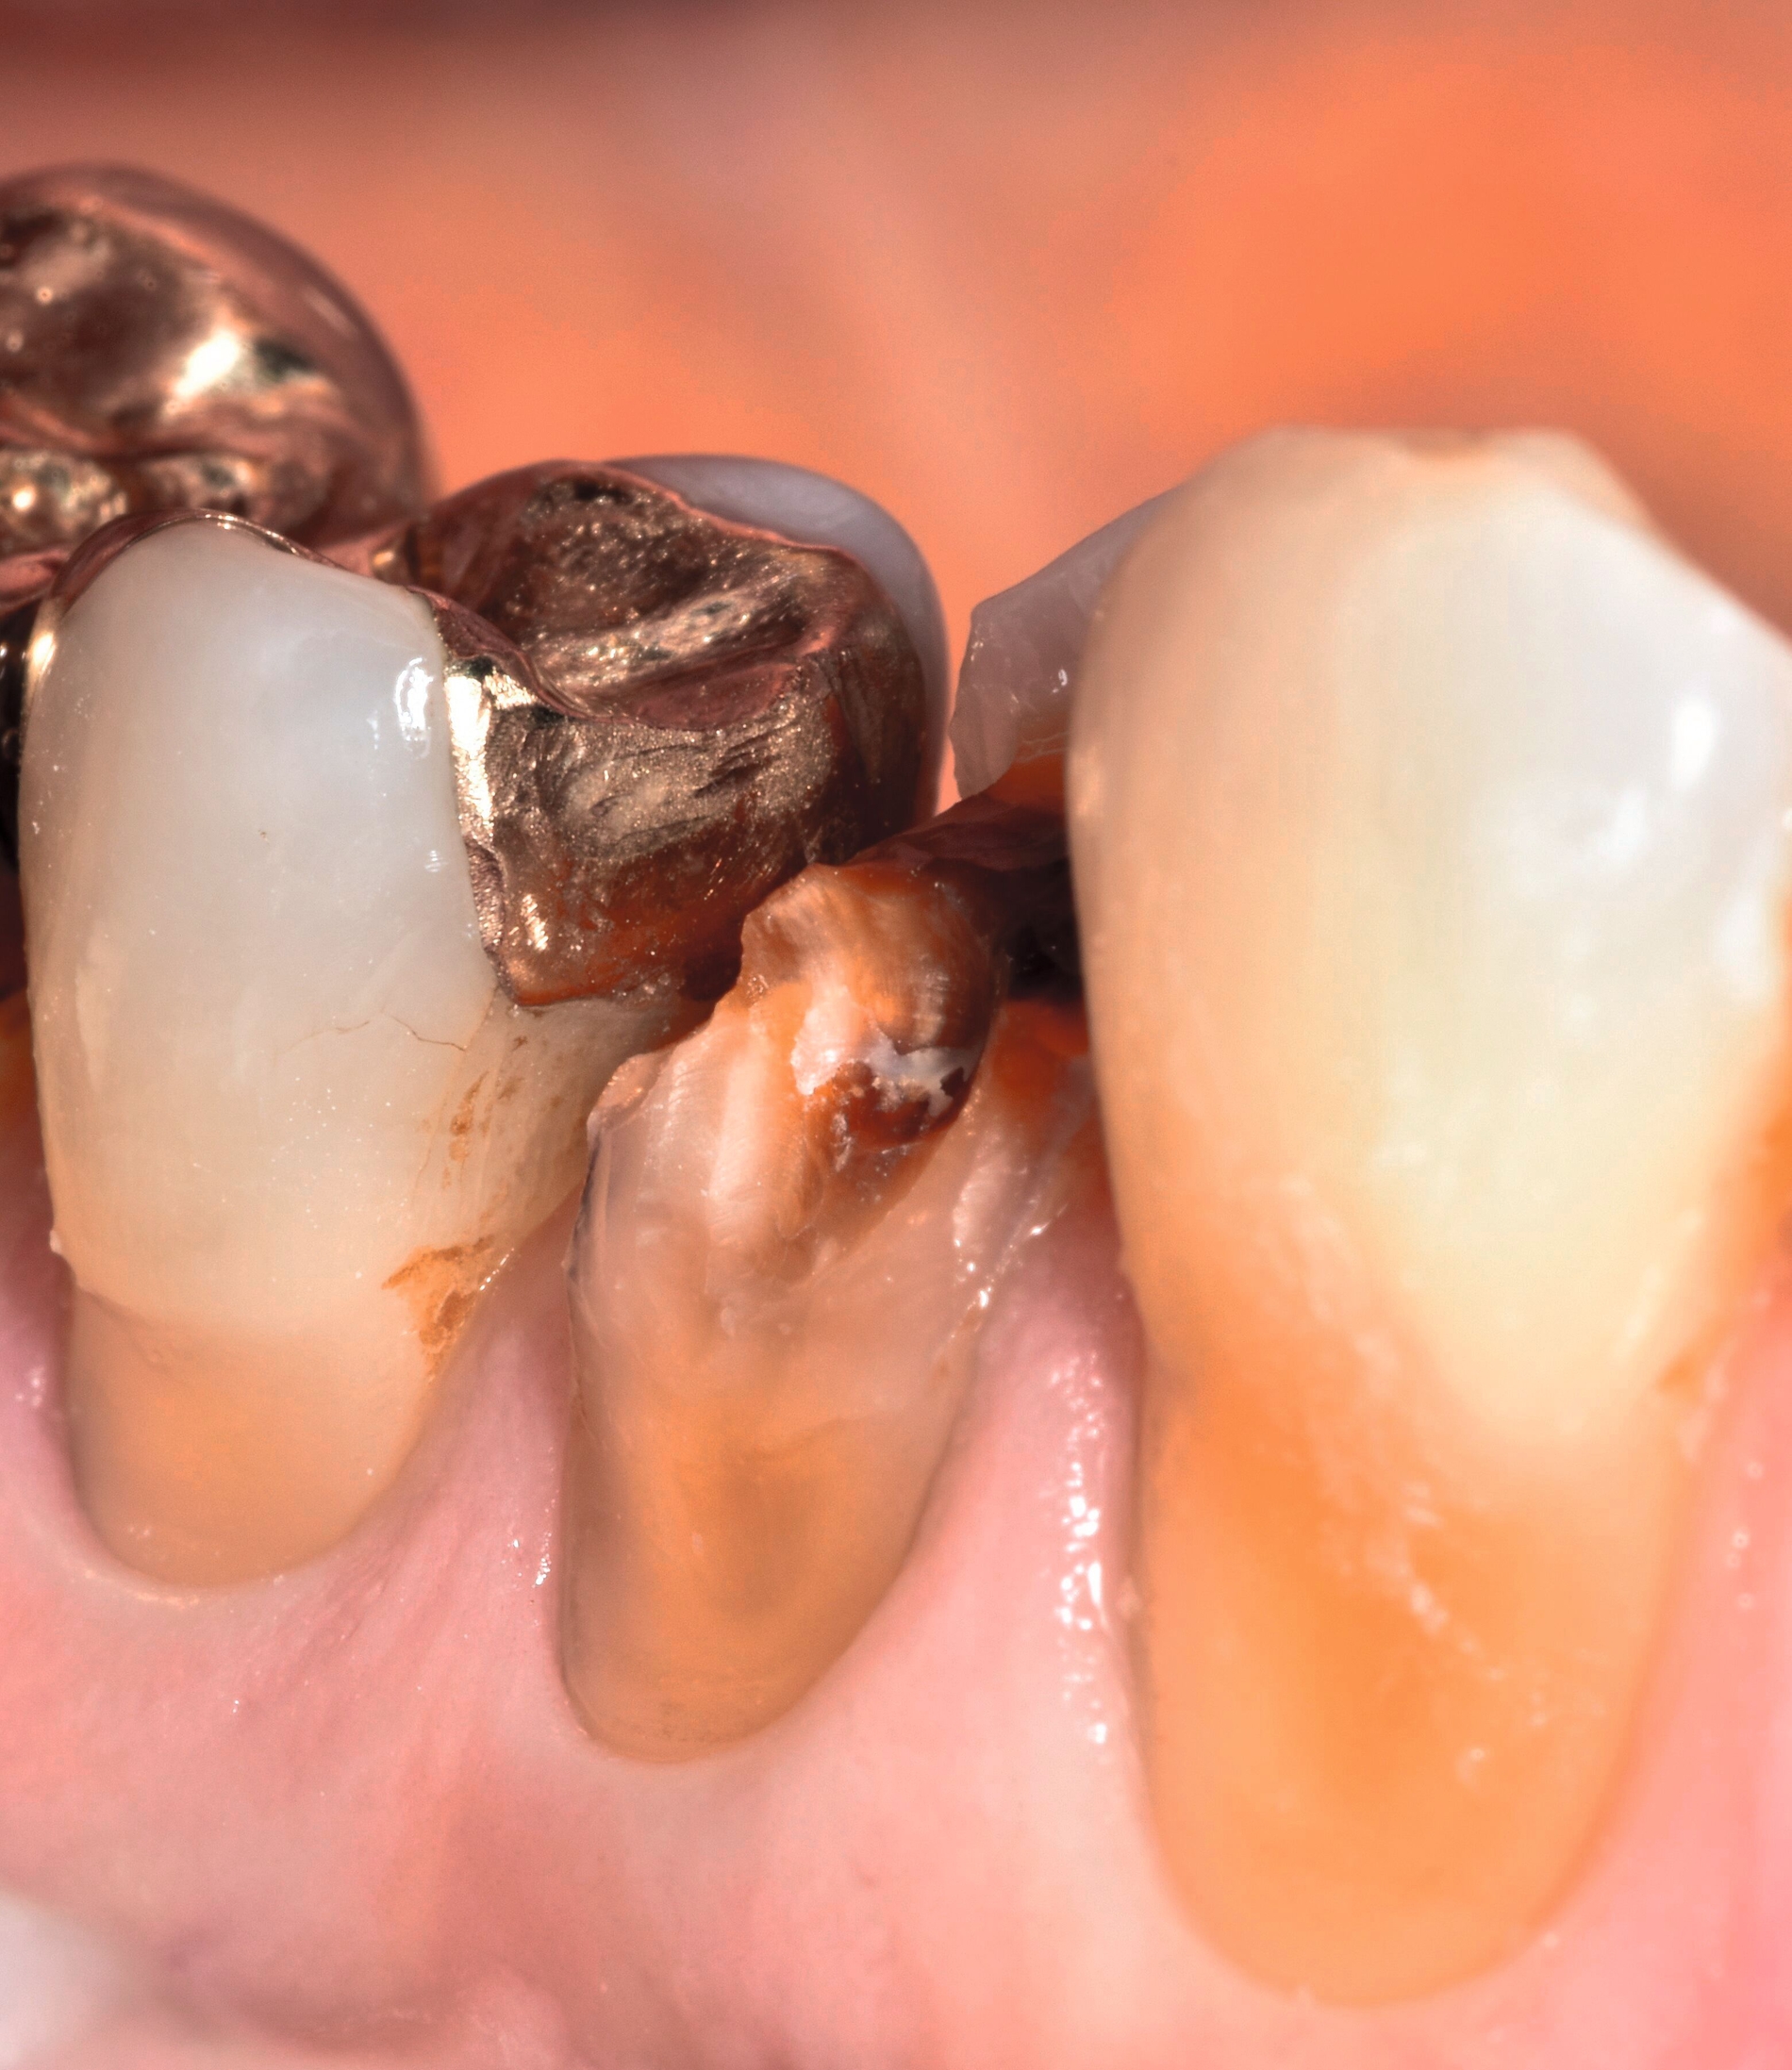

... mit Höckerersatz im Seitenzahnbereich

Für die Höckerüberkappung bedarf es eines ausreichend stabilen und abrasionsfesten Materials, das durch okklusale Kräfte belastet werden kann und die anatomische und funktionelle Rekonstruktion des Zahnes ermöglicht. Die Evidenz zur Verwendung von Kompositmaterialien bei Seitenzahnkavitäten mit Höckerersatz zeigt in mehreren Studien gute Überlebensraten [Deliperi et al., 2006; ElAziz et al., 2020; Fennis et al., 2014]. Van Nieuwenhuysen et al. [2003]berichtetenvon hohen Versagensraten sowohl bei Komposit- als auch bei Amalgamrestaurationen (30,4 Prozent beziehungsweise 28,1 Prozent). Diese Daten sind jedoch aufgrund der Verwendung älterer Kompositmaterialien als veraltet zu werten.

MERKE: Moderne Kompositmaterialien sind leistungsfähig und entsprechen den Prinzipien der minimalinvasiven Zahnmedizin. Insofern ist die Höckerrestauration mittels Komposit möglich (Abbildung 2).

Die Gruppe hat mit starkem Konsens die Empfehlung ausgesprochen, dass für Höcker-ersetzende Restaurationen insbesondere bei spezifischen Einflussfaktoren auf Zahn-, Mund- und Patientenebene (zum Beispiel eingeschränkte Compliance, schlechte Zugänglichkeit, komplexe funktionelle Rehabilitation) der Einsatz von indirekten Kompositrestaurationen erwogen werden kann.